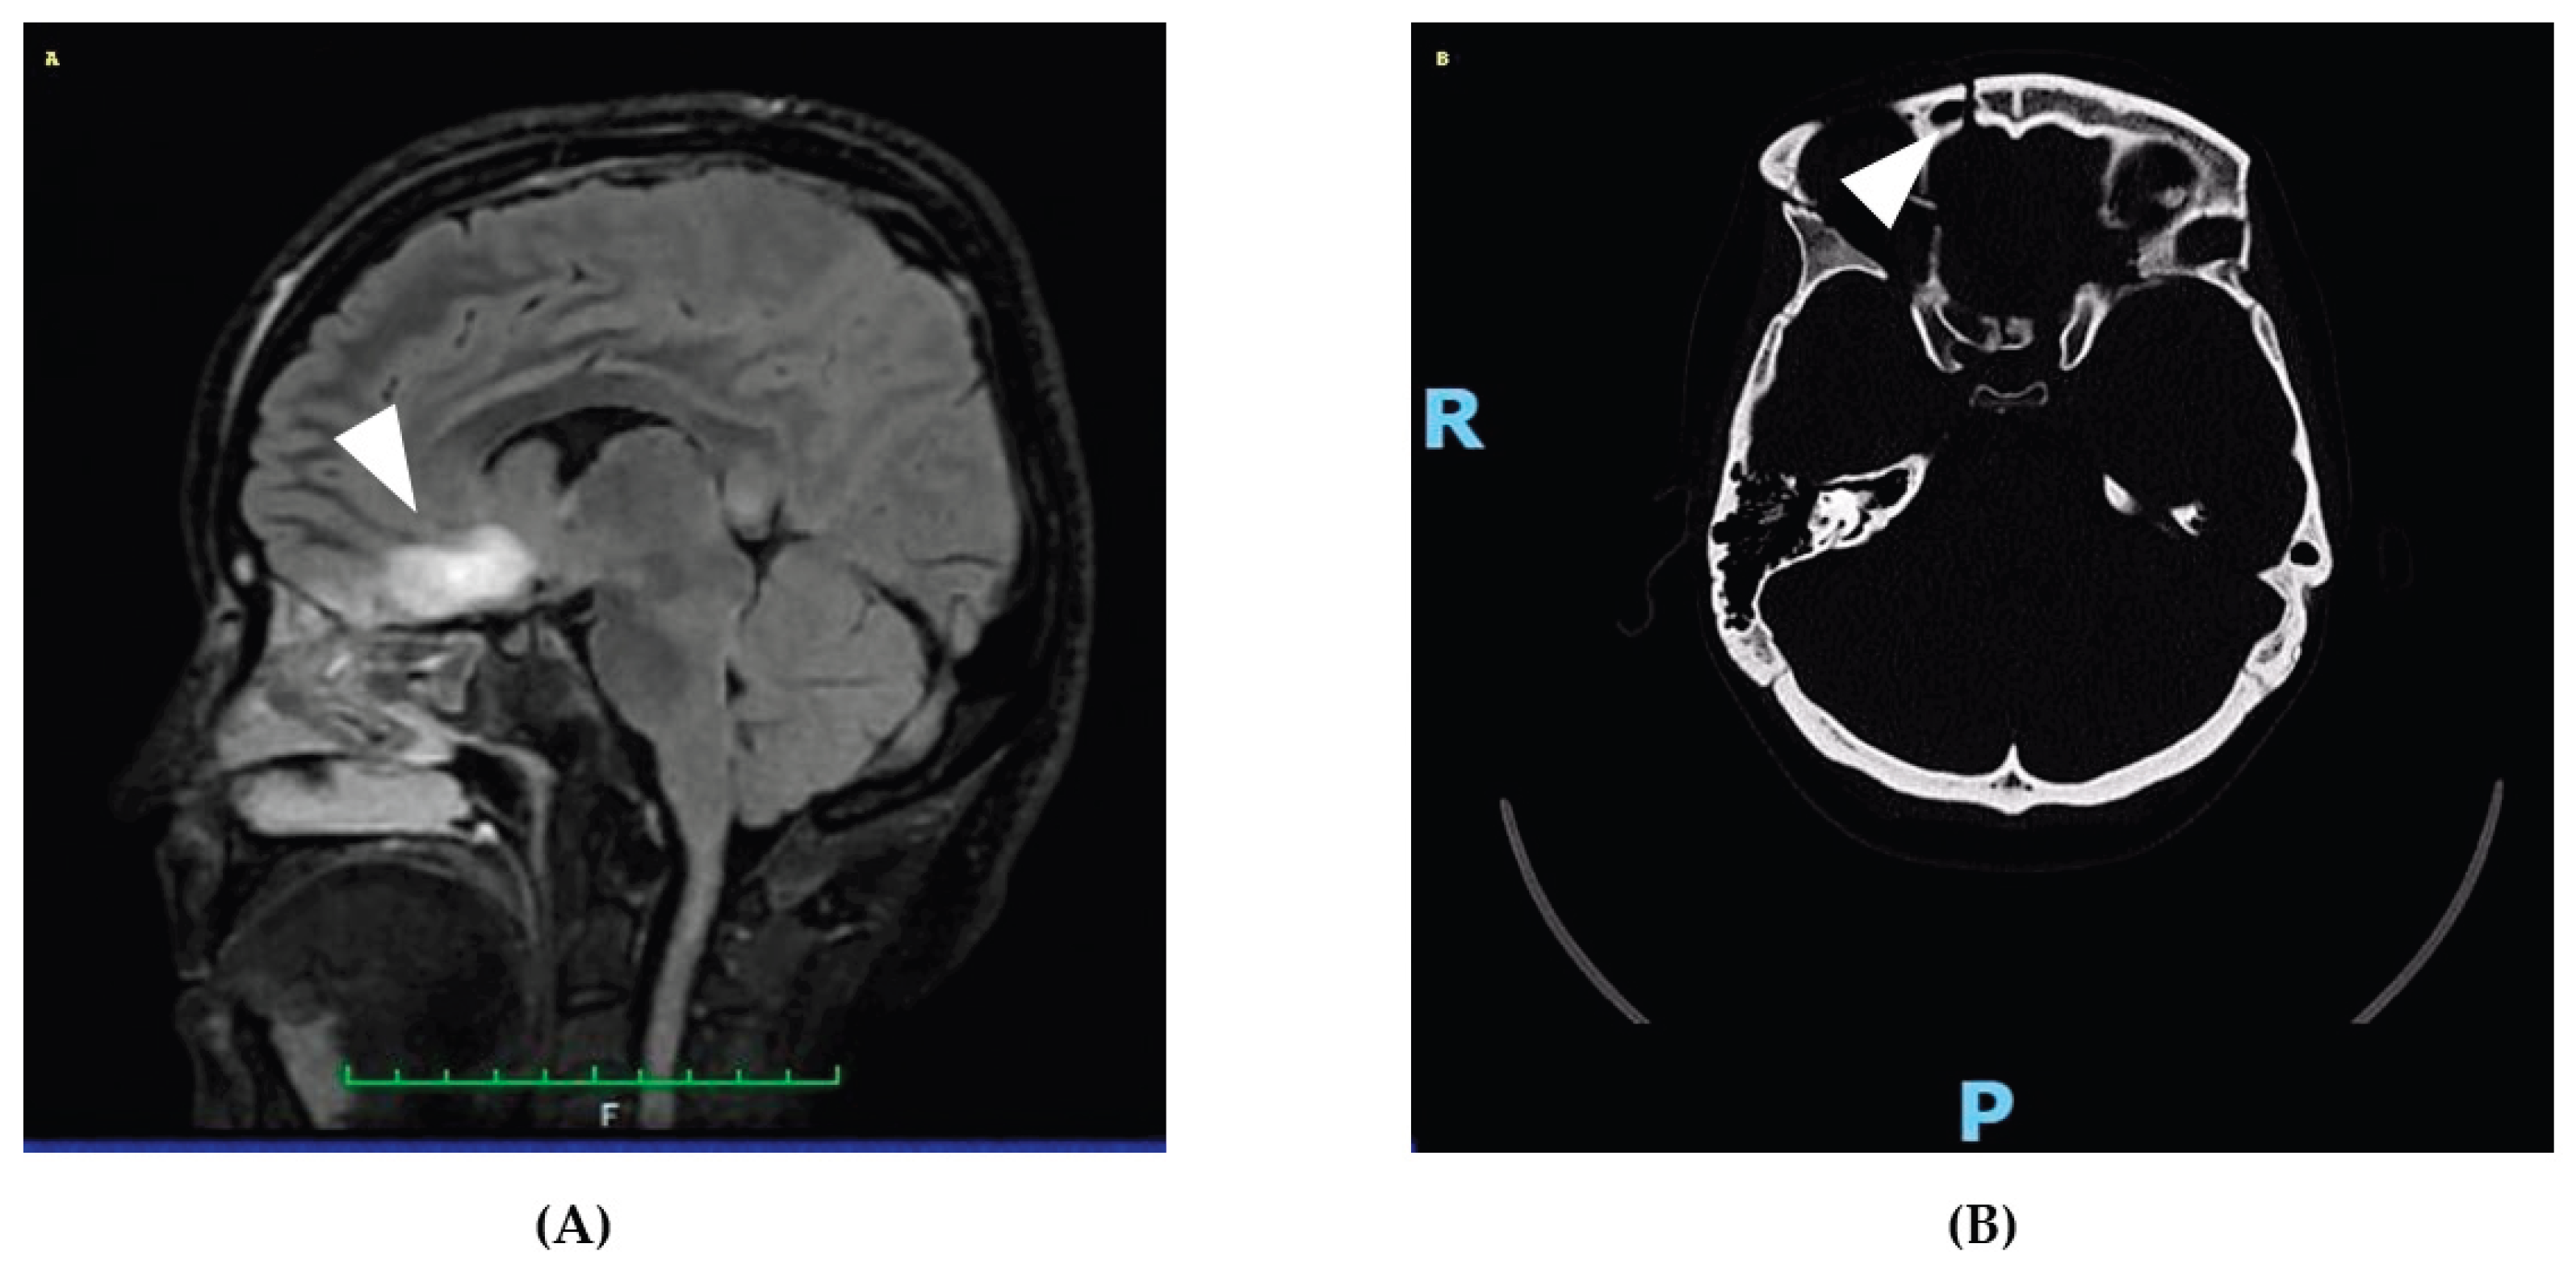

On April 21st, 2025, a 31-year-old woman was admitted to the emergency department following a high-impact car accident resulting in multiple traumatic injuries. She had no relevant past medical history and no smoking, alcohol, or substance use habits. She had completed 13 years of education and was employed. At initial evaluation, she appeared alert but partially oriented, exhibiting mild psychomotor agitation while remaining cooperative with medical staff. Whole-body computed tomography (CT) revealed bilateral intraparenchymal cerebral contusions, multiple splanchnocranial fractures with orbital involvement, paraseptal emphysema at the level of the pulmonary hilum, and focal lingual post-contusion consolidation. On April 24th, she was transferred to the neurosurgery department for further maxillofacial, ophthalmologic, and thoracic assessments. On April 27th, during hospitalization, the patient experienced a generalized comitial crisis accompanied by hyponatremia and new-onset anisocoria. A repeat CT scan showed no acute changes compared to previous imaging. Due to worsening neurological status, she was transferred to the intensive care unit, where she required intubation and underwent a brain MRI (Figure 1). MRI findings demonstrated artifacts consistent with diffuse axonal injury, along with cytotoxic edema involving the pituitary gland and the pericallosal pedicle. Following stabilization, she was extubated on May 6th and underwent a neurological examination. She was awake, cooperative, and able to move all four limbs symmetrically, with no signs of paresis or abnormal posturing. A mild reduction in muscle strength was observed, likely attributable to prolonged immobilization. Pupils were isochoric and reactive to light. Her neurological condition was deemed clinically stable, and she was transferred back to the neurosurgery ward. On May 15th, a maxillofacial examination confirmed consolidation of Craniomaxillofacial Orbitozygomatic (COMZ) fractures. A small, slightly displaced bone fragment persisted in the periorbital region but did not result in functional impairment, as confirmed by a subsequent ophthalmological evaluation. The patient nonetheless reported a persistent foreign body sensation and pain during ocular movements, likely due to impingement of the displaced fragment on the oblique ocular muscle. Given her progressive medical stabilization, on May 21st, 2025, the patient was transferred to the IRCCS Maugeri Institute for post-acute intensive neurorehabilitation (see Table 2 for Clinical Case Overview).

Figure 1. Representative neuroimaging findings following severe traumatic brain injury. (A) Sagittal FLAIR MRI showing a hyperintense lesion in the pericallosal region and pituitary stalk, consistent with diffuse axonal injury and cytotoxic edema. These findings support the neuroanatomical basis for the patient's cognitive, executive, and neuroendocrine symptoms. (B) Axial non-contrast CT scan revealing a right orbitozygomatic complex fracture with disruption of the orbital wall, consistent with the patient’s initial ocular motility impairment and diplopia. This image demonstrates the extent of craniofacial trauma sustained at the time of injury.